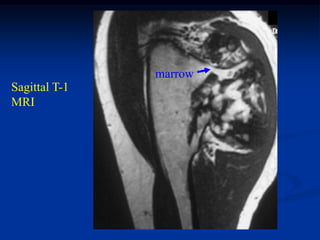

17 year male with osteochondroma humerus

marrow

Axial T-1 MRI

cap

Sagittal T-1

MRI